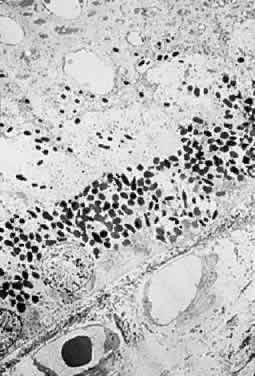

Clinicopathologic correlations of photic retinopathy have been reported by several investigators.16,75,76,144–146 Aware of prior studies by others on rats,25,147–150, Tso and coauthors reported the first of their series, performed on monkeys in 1972.75 They believed that the difference in their observations versus those published on rats might be related to the species of animal studied. Tso and coworkers created a model of chronic photic maculopathy through exposure to an indirect ophthalmoscope and found that significant changes were produced the first week after exposure, but a distinct maculopathy became evident only after an extended follow-up (5 months). They also described three stages in which this maculopathy occurs: initial degeneration in the first week, macrophagic response between the first week and first month, and repair and regeneration between the first and fifth month. Tso and associates also noted that, in the reparative phase, scarlike lesions noted clinically corresponded to proliferation of the RPE on a cellular level and, despite changes in the RPE, the overlying photoreceptors had regenerated. These clinicopathologic correlations led to more studies of macular response to light-induced injury. Histopathologic study of photic retinopathy in the human eye caused by exposure to light from the operating room microscope was reported by Green and Robertson in 1991.144 They describe the light and electron microscope findings of operating room microscope-induced maculopathy in a patient's eye after exposure to the light source for 60 minutes, 72 hours before enucleation for an iris melanoma (Figs 5 through 8). Findings in this acute form of photic retinopathy occurred mainly at the level of the RPE and photoreceptor layer and included the following: localized necrosis of the RPE; loss of the apical villi, plasma membranes, and cytoplasmic organelles of the RPE cells; extrusion of the retinal pigment epithelial pigment granules; and extensive disruption of the outer lamellae of the photoreceptors. Swollen mitochondria were present within the photoreceptor inner segments. Although this study was designed to address the issue of acute light-induced retinal damage, the additional finding of thinned retinal pigment epithelial cells, which apparently had migrated under injured RPE cells, suggests that a reparative process had already begun. The findings of Green and Robertson are consistent with those of Jaffe and coworkers reported in primates.146

Fig. 7. Electron-microscopic view of photic retinopathy with extensive derangement of the outer segments of the photoreceptors with distention (main figure), distortion, compaction, partial disintegration of the lamellar disks and disruption of plasma membranes. The inner segments of the cones are moderately swollen and the mitochondria are markedly distended. Inset shows details of the swollen mitochondria. (Green WR, Robertson DM: Pathologic findings of photic retinopathy in the human eye. Am J Ophthalmol 112:520, 1991)

Fig. 8. Electron-microscopic view of photic retinopathy. The retinal pigment epithelial cells are severely damaged with loss of plasma membranes, apical villous processes, basal infoldings and extrusion of pigment granules. Overlying the retinal pigment epithelial cells, a variably dense granular material containing fragments of outer segments is observed. (Green WR, Robertson DM: Pathologic findings of photic retinopathy in the human eye. Am J Ophthalmol 112:520, 1991)